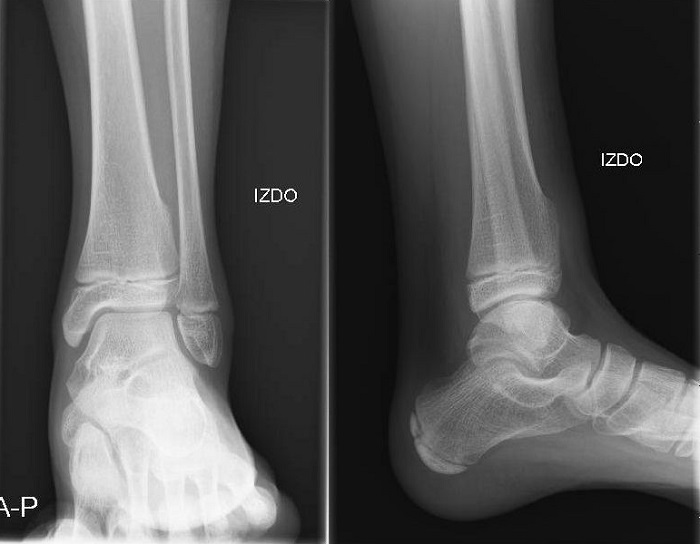

Paciente de 12 años con antecedentes de quiste óseo en el húmero derecho, intervenido a los tres y los 6 años de edad, y enfermedad de Crohn en tratamiento actual con adalimumab 20 mg cada 14 días, acude por dolor en pierna izquierda tras traumatismo casual. En la exploración, presenta leve aumento de temperatura local en tobillo izquierdo, sin dolor ni eritema, y destaca palpación de reborde óseo en maléolo externo con movilidad conservada. En la radiografía se observa una tumoración en la parte distal de tibia izquierda asociada a aumento de partes blandas (Fig. 1). Debido a los antecedentes de patología ósea y a los hallazgos radiológicos, se deriva a la paciente a traumatología, donde se diagnostica de osteocondroma en tibia distal izquierda. Indican vigilancia periódica y nueva derivación en caso de observar crecimiento de la lesión.

Figura 1. Radiografía

En este caso, la paciente se ha mantenido en todo momento asintomática y el tumor se ha encontrado de manera casual tras un traumatismo. Hay que destacar la importancia de la exploración física tras traumatismos casuales y de la correcta valoración de las pruebas de imagen.